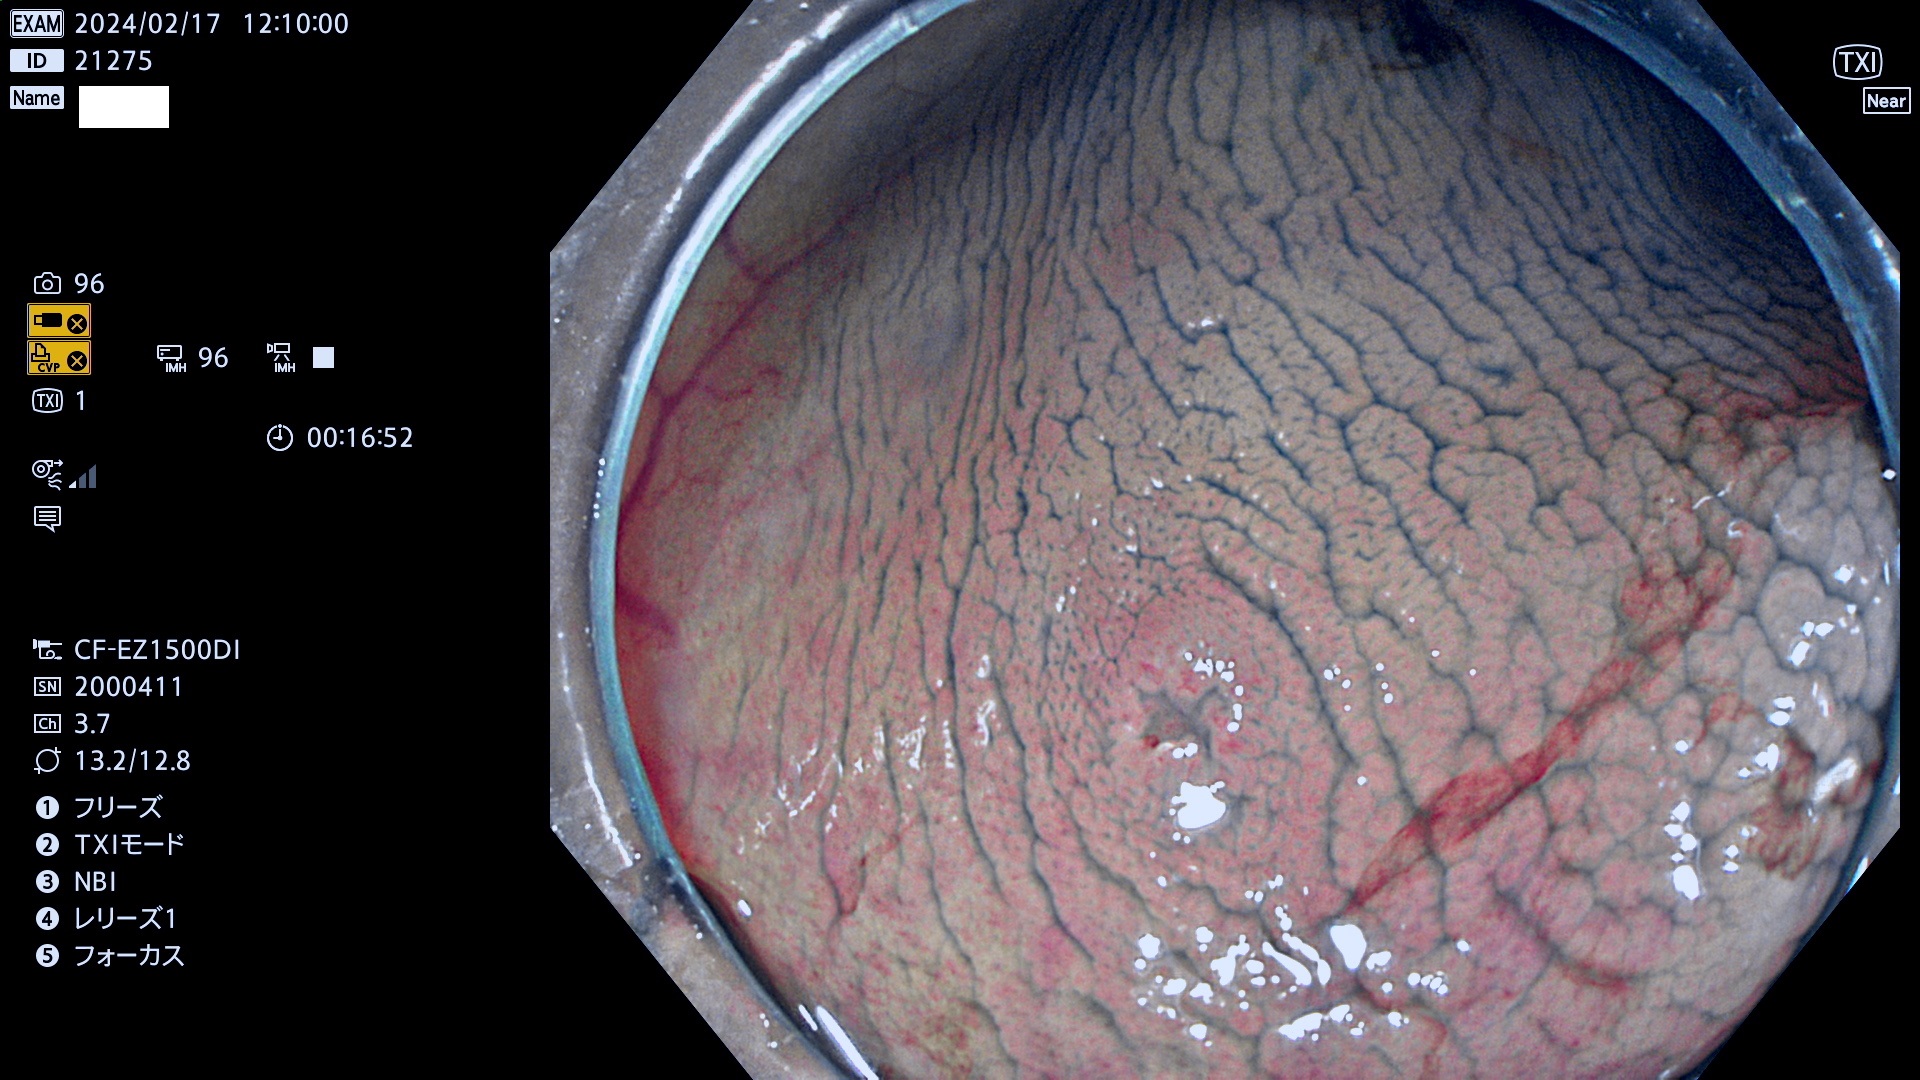

今週のUb、Uc型腺腫

表面型腺腫(Flat Adenoma)の中で、完全に平坦な物をUb、陥凹している物をUcと呼びます。平坦隆起型(Ua)よりも、発見が難しく危険な病変です。

毎週の検査(木・金・土・日)に発見されたUb、Uc型・腺腫を、その週の日曜の夜にUPし1週間、提示します。

抽出の対象期間 2024年2月15日(木)〜2月18(日)の4日間(40件の検査)10件 (10/40=25%)